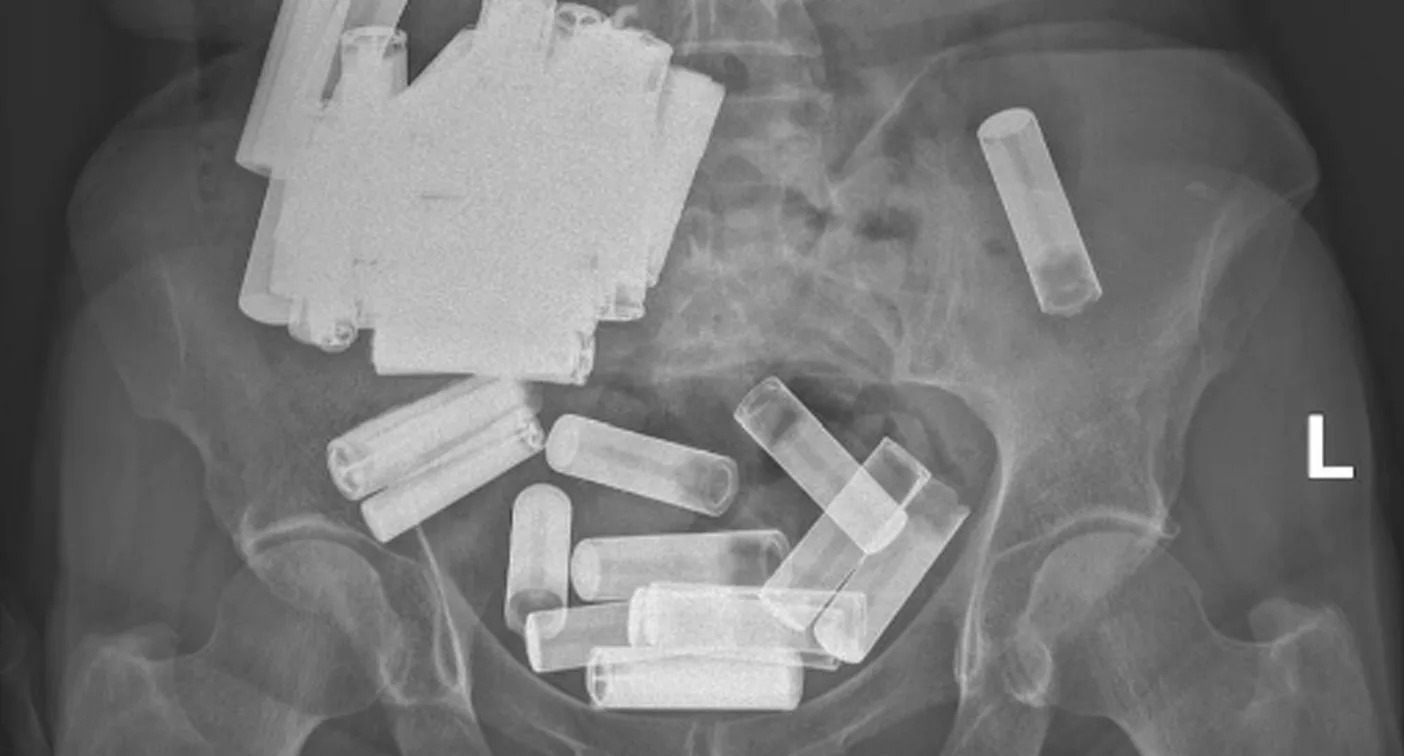

>>218437834those look more like batteries doe